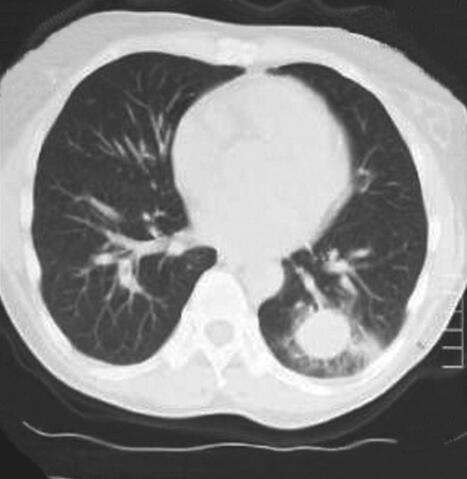

患者,女,52岁,新疆巴楚县农民,维吾尔族。因“间断发热6个月,发现肺部阴影和眼部肿物2个月”于2012年4月10日收入院。患者于6个月前出现间断发热,体温39~40.5℃,伴畏寒、寒战,持续30分钟至3小时可自行降至正常,发热时间间隔2~10天,曾于当地医院行胸片检查“未见明显异常”,给予“头孢类”抗生素治疗无效。2个月前出现双眼不适、右眼视力下降,眼科检查示“右眼肿物”,切除肿物病理示“少许坏死组织”。术前胸片检查发现“右肺上野圆形密度增高影”(图1);肺CT示“右肺上叶团块影,周围见分叶征,内见空洞;左肺下叶球形占位影,周围散在片状渗出影”(图2),遂于当地医院住院诊治。行支气管镜检查发现“右上叶肿物生长,各分支管腔狭窄,右中、下叶各支通畅;左支气管各支通畅”。行左下叶支气管刷检,病理报告“大片炎性渗出及坏死组织”。进而就左肺下叶病变行经皮肺穿刺活检术,病理报告“部分肺泡上皮增生,变性坏死组织炎性细胞浸润”。发热及肺部肿物诊断未明。患者因眼部肿物切除后出现右眼发红、疼痛、视力下降,10天前于我院眼科就诊,诊断为“右眼角膜穿孔、右眼眶蜂窝织炎”,行右眼摘除术,眼球病理示“中性粒细胞浸润,部分组织坏死伴脓性渗出物”。术后5天出现消化道大出血,肠镜示“结肠多发溃疡”,肠黏膜病理示“慢性炎症”,给予输血、止血治疗后出血停止。因发热和肺部肿物原因不明,为进一步诊治收入我科。近1个月患者发热呈持续性,体温39~40℃。10天前眼科术前复查胸片显示“右上叶不张”(图3);肺CT发现“右肺上叶阻塞性肺不张,左肺团块影,周围见片状渗出影”(图4)。患者发病以来,食欲不振、乏力明显,近半年体重下降5kg。

图3 胸片

右肺上叶不张,左肺下叶类圆形致密肿块影,边缘模糊,周围浅淡斑片影